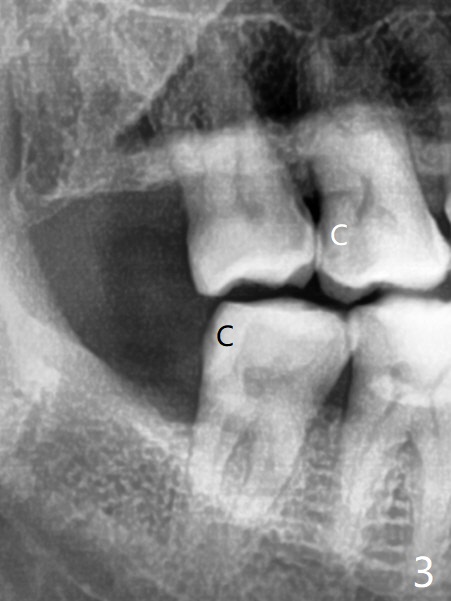

51岁男牙周炎,坚持他有蛀牙,全景片和根尖片显示右上第一右下第二磨牙远中龋(图一,二 *)。稍微分离右下智齿颊侧牙龈,分冠拔除,纱布塞入拔牙窝,好像第二磨牙远中龋去除比较容易,所以决定同期树脂修复。为了防止树脂脱落,去除龋坏后,在咬合面制备鸠尾。当时为了图省事,没有使用成型片,反而费时,尽管用纱布止血隔离,效果不好,徒手堆树脂不方便,尤其是牙龈处。下次必须用二号成型片,剪去近中牙龈部分,让远中部分完全入位,特别是牙龈缘。最后在拔牙窝放置胶原塞,缝合,防止干槽症。七天后缝线消失,伤口仿佛愈合,右下七没有症状。右上第一磨牙DO树脂修复,好像接近远中舌侧牙髓角,术后全景片(图三)似乎证实这一点。